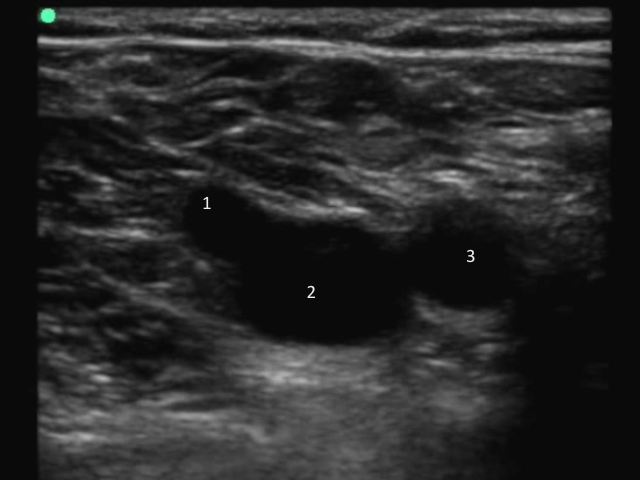

DVT:画像1 CFV Saph junct labeled